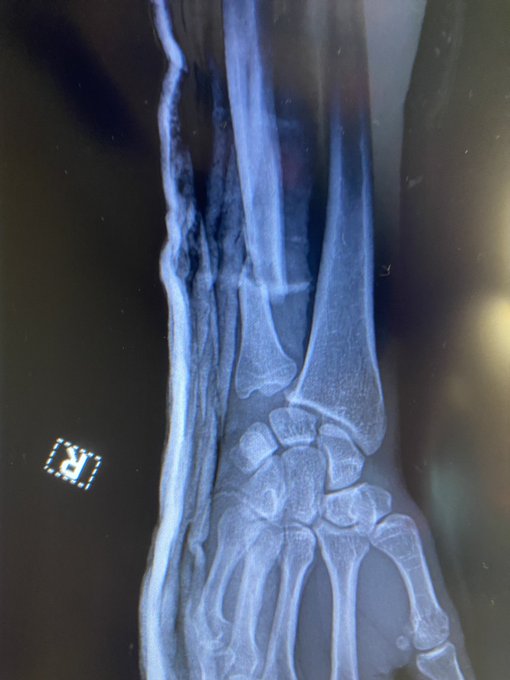

Det var ikke blot en stor bedrift, at han vandt. Det blev kun gjort til en endnu større bedrift af det faktum, at han gjorde det med en brækket arm. Søndag delte han selv et røntgenbillede af armen, som tydeligt er brækket.

"Jeg tror, det var et spark i første runde, der kan have givet den et lille knæk. Hvis du ser på det, kigger jeg ned på min arm lige da runde to starter. Det gør jeg, fordi den ikke reagerer, som jeg vil have den til. I anden runde lander han et par spark mere, og jeg tror, det brækker den."

"Jeg følte det i anden runde. Jeg tænkte: 'Der er noget heroppe'. Jeg kunne ikke mærke min højre hånd. Det var først i tredje runde, jeg fik ham ned, og jeg prøvede at afslutte det. Jeg fulgte op med slag."

"Jeg slog med min højre og følte, at den gik helt skævt. Hele min højre arm gik bare død. Det var ikke sådan, jeg ville vinde. Jeg styrede ham på toppen med højre albue, og blev på toppen, mens jeg slog ham med min venstre hånd."